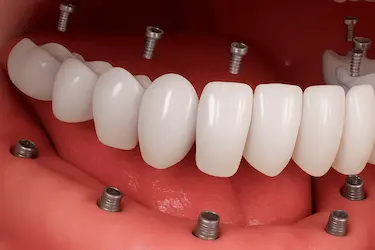

En nuestra clínica en Murcia realizamos la técnica de carga inmediata en implantes dentales, un procedimiento avanzado que permite colocar una prótesis fija provisional el mismo día de la cirugía.

La carga inmediata puede aplicarse tanto en casos individuales, por ejemplo, al reponer una sola pieza, como en rehabilitaciones completas, donde el paciente necesita una dentadura inmediata sobre varios implantes.

En la fecha indicada, procedemos a la extracción de la pieza si fuese necesario o directamente a la colocación del implante.Se trata de un tornillo de titanio que se fija al hueso maxilar o mandibular y actúa como la raíz del diente. La intervención se realiza con anestesia local y es un procedimiento indoloro y ambulatorio. - Colocación de la prótesis provisional el mismo día.

En los tratamientos de carga inmediata, colocamos en ese mismo acto quirúrgico una prótesis provisional diseñada a medida.Esta prótesis permite recuperar de forma inmediata la estética y la función masticatoria, además de favorecer una correcta cicatrización y el proceso de osteointegración. - Fase de osteointegración y controles.